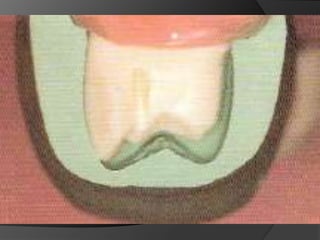

¾ ANTERIORES

¾ ANTERIORESRequieren más  tiempo y destreza que para coronas completas y no son para todos los dientes ni para todos los pacientesIndicación: En puentes cortos con pilares relativamente libres de restauraciones y de caries. Contraindicado en sobremordidas profundas